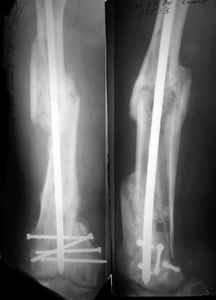

1. Percutaneous nailing is truly minimally invasive technique, but, unfortunately, nails are not reliable in many hands.

Attached are few examples from our Hospital:

A. Difficult reductions, even in retrograde nailing (my preference, easier control of "small" distal fragment) and it is much, much harder to do it anterograde (Alex, do you have one good case in your collection of anterograde nailing in very distal fractures - as you have suggested that I

should have done it in my previously posted case?

Malpositioning is much too common (recurvatum, varus - valgus).

B. Fixation loosening: distal cutting of the nail, non-unions do happen (cases attached).

Locking Plating has more distal screws than any nail, fixed angles and provides much better fixation, especially in osteoporotic bone.